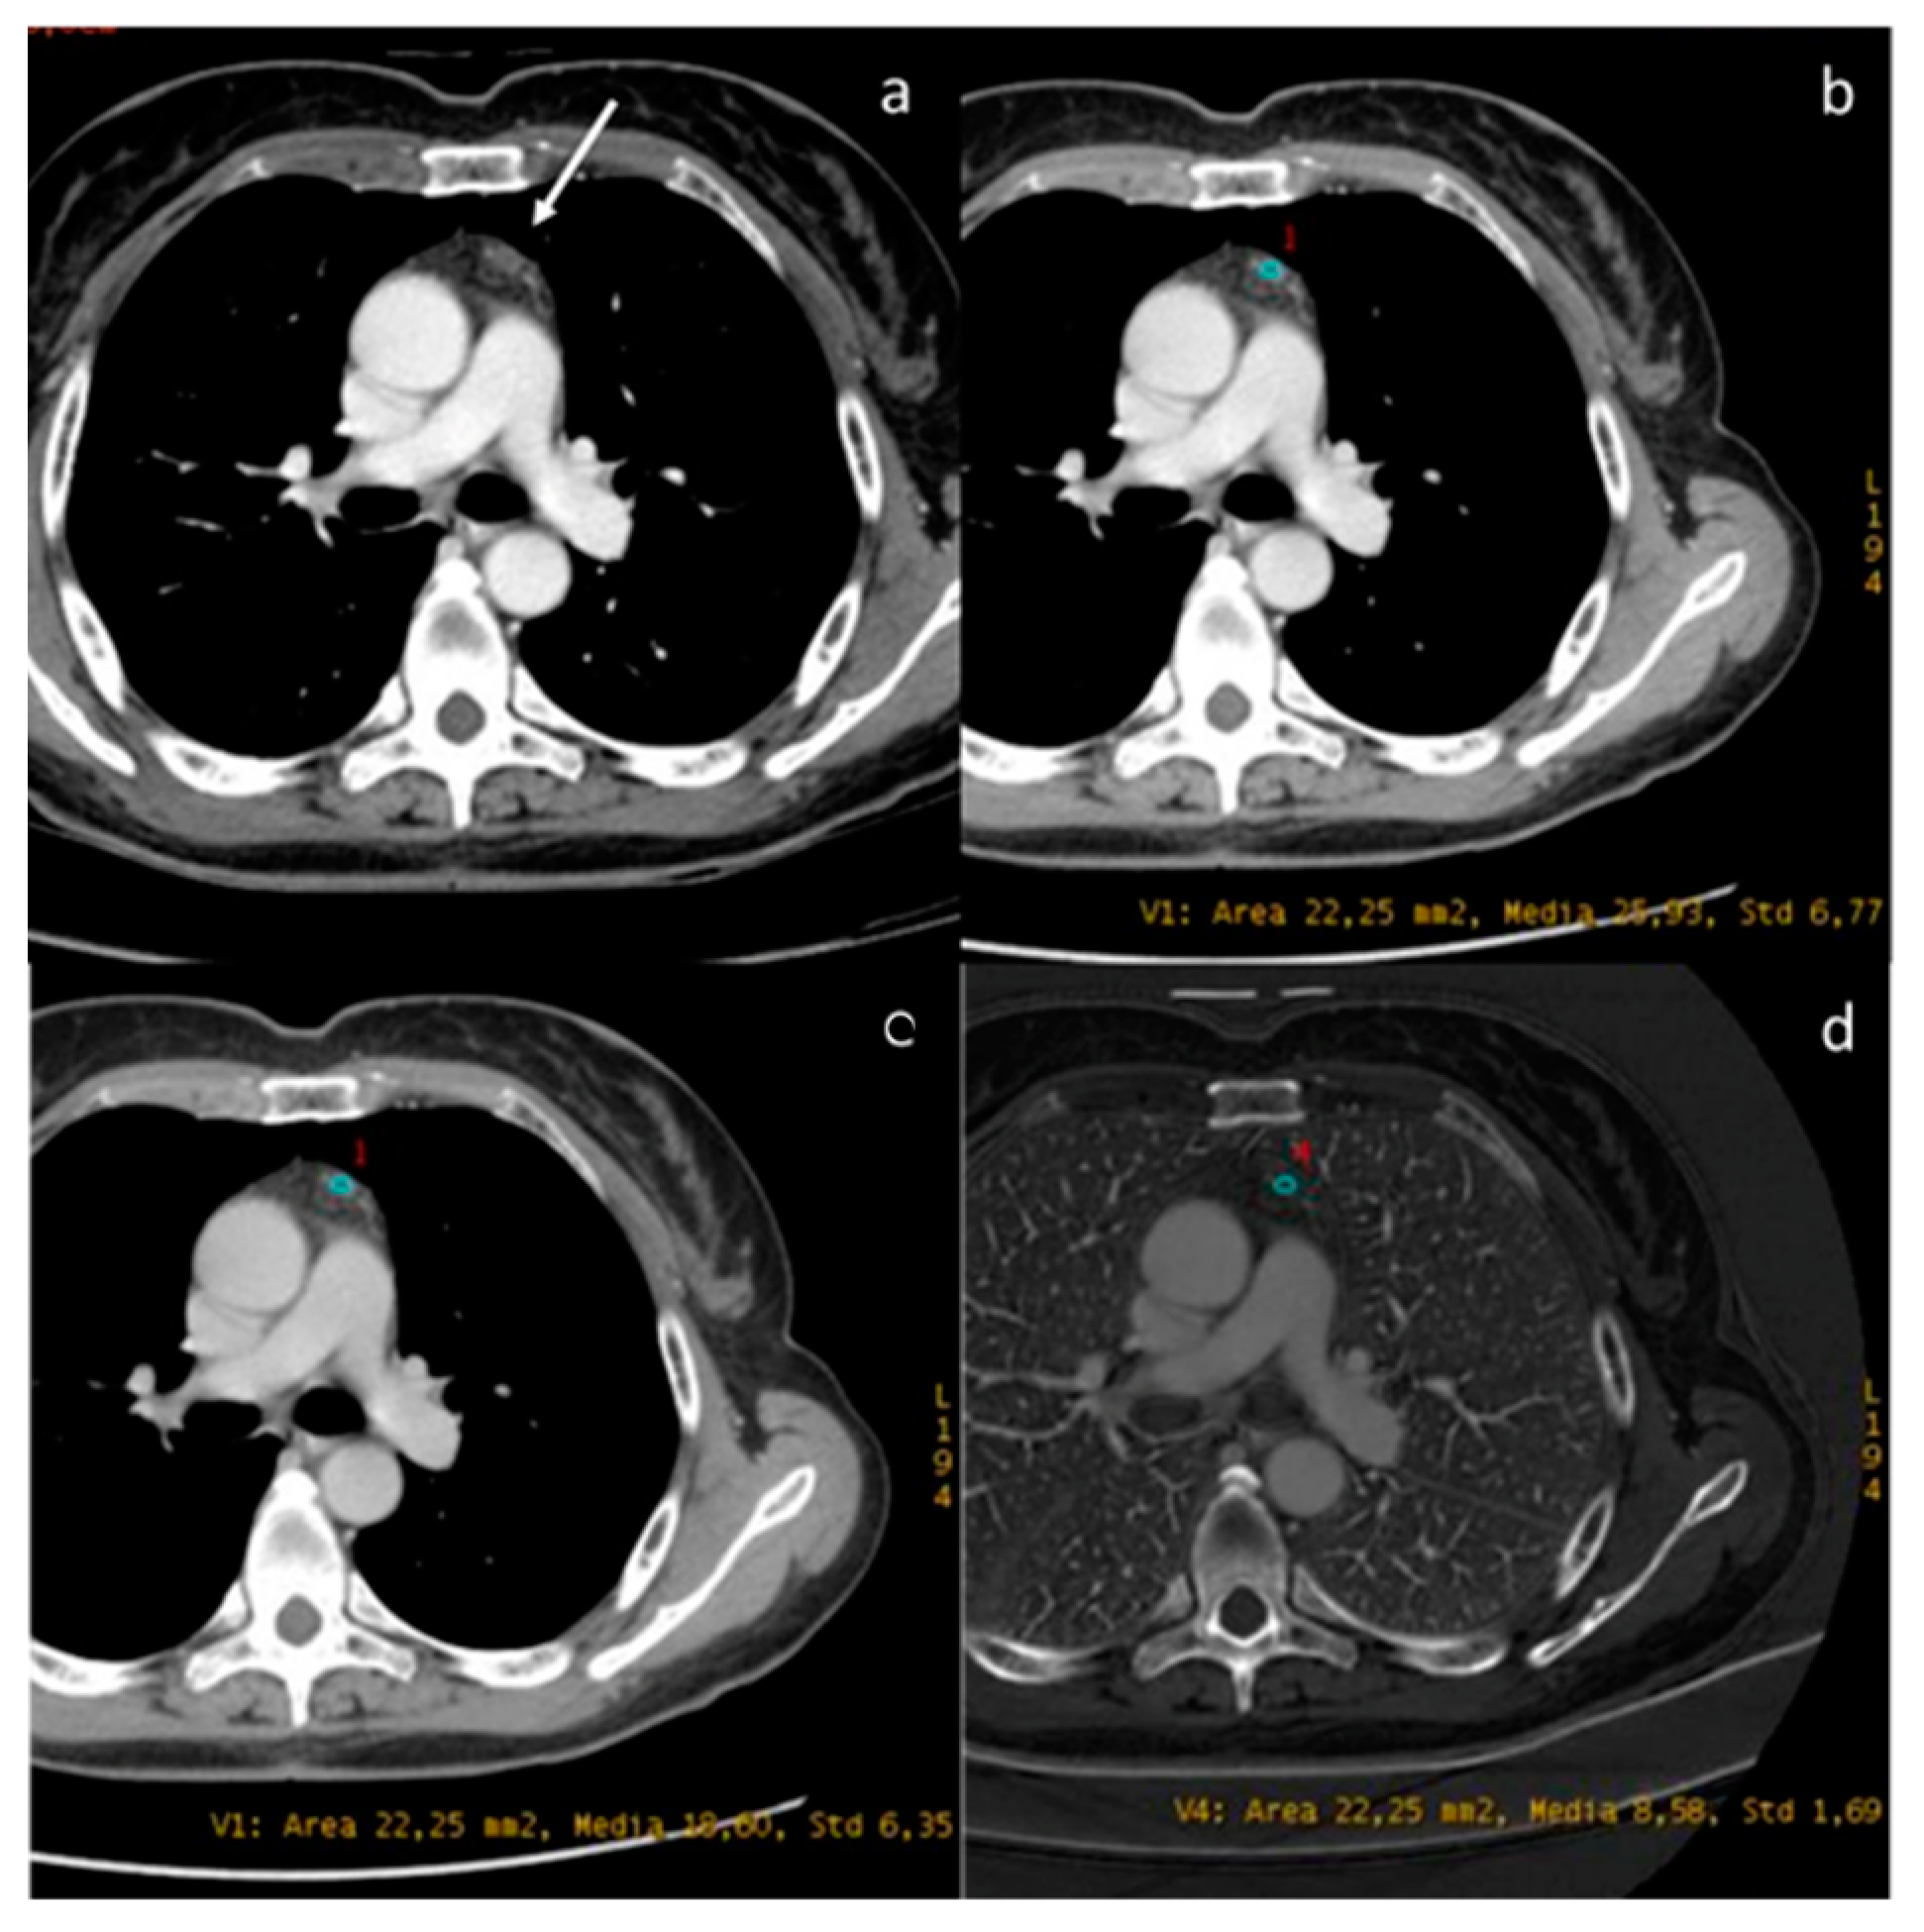

| Si-Mohamed et al. [67] Retrospective study | France | To assess whether VNC images derived from contrast dual-layer DECT images could replace TNC images for aortic intramural hematoma diagnosis in acute aortic syndrome imaging protocols by performing quantitative as well as qualitative phantom and clinical studies. | 21 | IQon, Philips Healthcare No C.I. | Dual-layer -DECT offers similar performances with VNC and TNC images for intramural hematoma diagnosis without compromise in diagnostic image quality. VNC imaging with dual-layer DECT reduces the number of acquisitions and radiation exposure in acute aortic syndrome imaging protocol. |